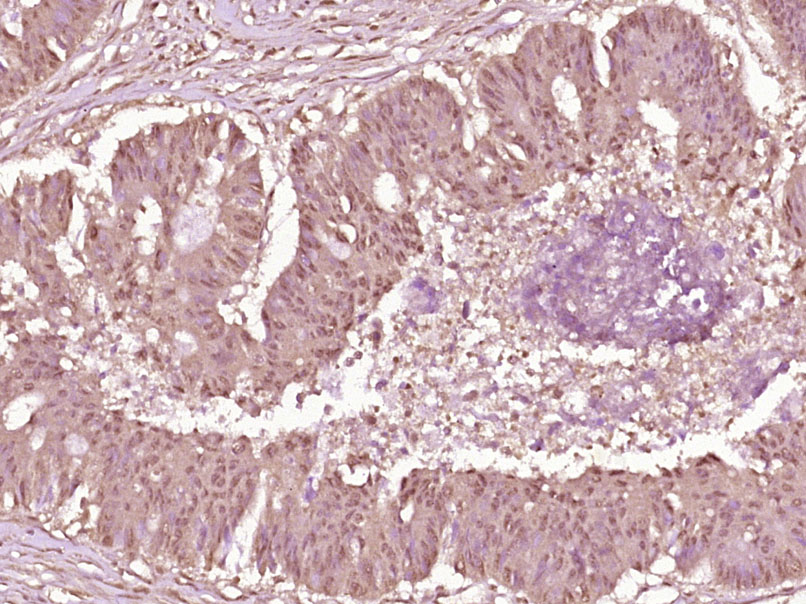

Paraformaldehyde-fixed, paraffin embedded (human colon); Antigen retrieval by boiling in sodium citrate buffer (pH6.0) for 15min; Block endogenous peroxidase by 3% hydrogen peroxide for 20 minutes; Blocking buffer (normal goat serum) at 37°C for 30min; Incubation with (Phospho-cdc25A (Ser178) ) Polyclonal Antibody, Unconjugated (bs-3095R) at 1:200 overnight at 4°C, followed by operating according to SP Kit(Rabbit) (sp-0023) instructionsand DAB staining.